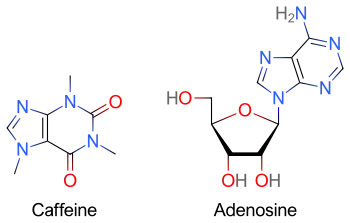

Methylxanthines (e.g. caffeine, found in coffee, theophylline in tea, or theobromine, found in chocolate) have a purine structure and bind to some of the same receptors as adenosine.[14] Methylxanthines act as competitive antagonists of adenosine and can blunt its pharmacological effects.[15] Individuals taking large quantities of methylxanthines may require increased doses of adenosine.